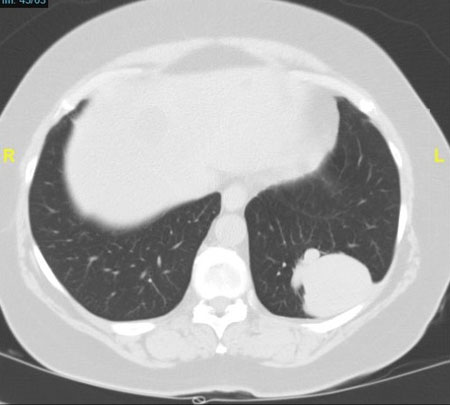

Figure 3. CT scan. a. coronal reformatted image shows bilateral irregular flame-shaped nodular opacities (red arrows) along with peribronchovascular distribution (white arrows), relative sparing of the periphery; b. axial in lung window. The tendency of KS to grow in the axial interstitium (arrow). No significant mediastinal lymphadenopathy is seen. No pleural effusions are seen. c. axial in lung window. Poorly defined lung nodules. Central airways are patent. No ground-glass opacities.

This case was subsequently investigated with a CT scan of the chest. Please review the CT scan (Fig. 3). It shows that there are bilateral perihilar consolidations with air bronchograms. Irregular nodules or masses with a peribronchovascular distribution, often called "flame-shaped" lesions, are very characteristic.

CT shows multiple bilateral symmetric “flame-shaped” or ill-defined nodular lesions peribronchovascular distribution. Ground-glass opacities and thickening of the interlobar septal walls may be seen.